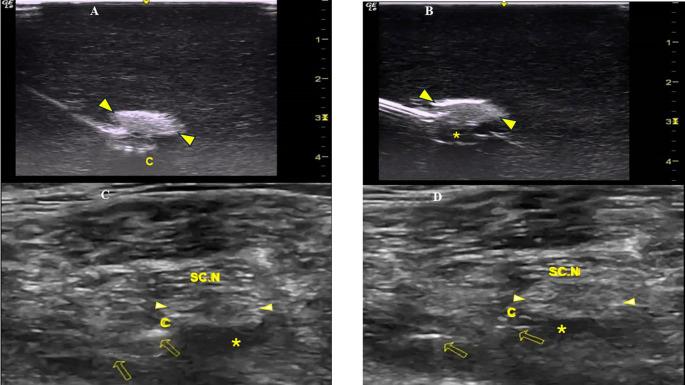

We conducted a randomized study of two methods of perineural catheter advancement in a sciatic nerve block Blue Phantom simulator. Two groups of twenty catheters each (method A and method B) were evaluated under real-time ultrasound imaging. The needle in-plane/nerve in-short-axis technique was applied. In method A the catheter was advanced beyond the needle tip with the integral stylet extending along its entire length; in method B the catheter was advanced after its integral stylet was retracted by 6 cm, thus providing flexibility to the catheter's distal end. Additionally, to assess the procedural effectiveness of method B coiling technique, a pilot study was conducted examining 25 perineural catheters coiled underneath the sciatic nerve in trauma-orthopaedic patients to document any catheter tip displacement from their initial position (for 36 hours postoperatively).

In the simulation study, method B led to a significantly higher percentage (18/20:90%) of coiled catheters than method A (3/20:15%). Two coiled catheters of method B were found kinked/obstructed. In our patients, after catheter insertion, the distal end of 2/25 (8%) coiled catheters was obstructed. One perineural catheter was dislodged. For the remaining 22 (88%) catheters, ultrasound imaging demonstrated that local anaesthetic infusion made contact with the sciatic nerve, indicating no displacement of the catheter's distal end postoperatively.

我们在坐骨神经阻滞蓝色幻影模拟器中对两种神经周围导管推进方法进行了随机研究。在实时超声成像下评估两组各20根导管(方法A和方法B)。采用针平面/神经短轴技术。在方法A中,导管随着一体式导丝沿其全长延伸而推进到针尖之外;在方法B中,导管在其一体式导丝缩回6 cm后推进,从而使导管远端具有灵活性。此外,为了评估方法B盘绕技术的操作效果,进行了一项初步研究,检查25根在创伤骨科患者坐骨神经下方盘绕的神经周围导管,以记录导管尖端相对于其初始位置的任何移位情况(术后36小时)。

在模拟研究中,方法B导致盘绕导管的百分比(18/20:90%)显著高于方法A(3/20:15%)。发现方法B的两根盘绕导管出现扭结/阻塞。在我们的患者中,导管插入后,2/25(8%)根盘绕导管的远端出现阻塞。一根神经周围导管移位。对于其余22根(88%)导管,超声成像显示局部麻醉药注入与坐骨神经接触,表明术后导管远端无移位。